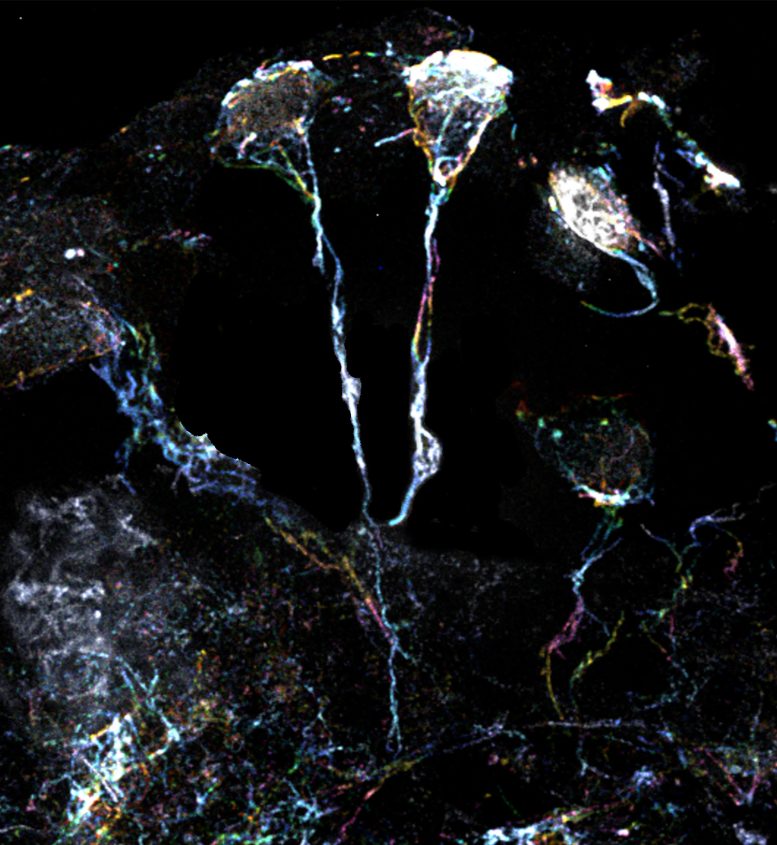

科學(xué)家團隊使用放大倍數為10倍的超分辨率顯微鏡檢查了果蠅休眠神經(jīng)干細胞的標志性微小纖維結構。這些細微結構的直徑約為1.5μm(比人類(lèi)頭發(fā)的直徑小20倍),是從細胞體延伸出來(lái)的突起,富含肌動(dòng)蛋白或蛋白質(zhì)細絲。一種特定類(lèi)型的Formin蛋白可以激活這些細絲并使其組裝。

果蠅大腦中處于休眠狀態(tài)的神經(jīng)干細胞具有富含肌動(dòng)蛋白絲的突起

果蠅大腦中處于休眠狀態(tài)的神經(jīng)干細胞具有富含肌動(dòng)蛋白絲的突起。圖片來(lái)源:杜克-新加坡國立大學(xué)醫學(xué)院